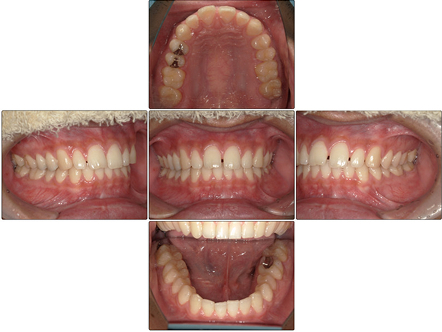

お口の中全体の写真

After

お口の中全体の写真After

治療結果

上のすきっ歯は矯正治療前よりも閉鎖され、前歯が全体的に整って綺麗な歯並びとなりました。